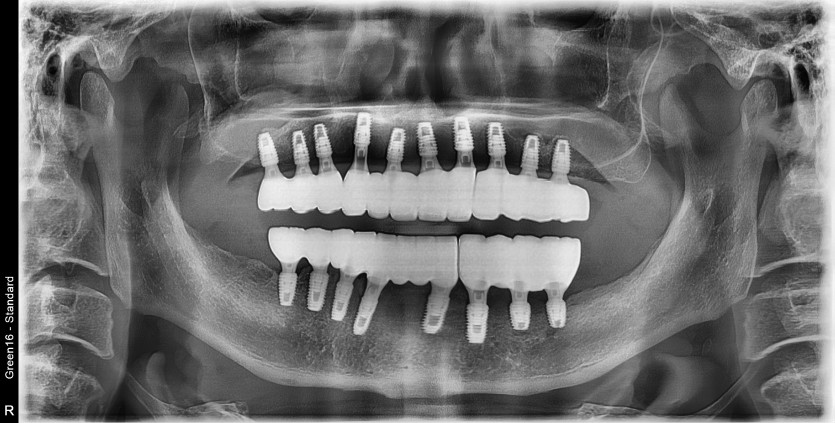

만 59세 전체 임플란트 증례

전체 임플란트 증례입니다.

18개의 임플란트로 완성하였습니다.